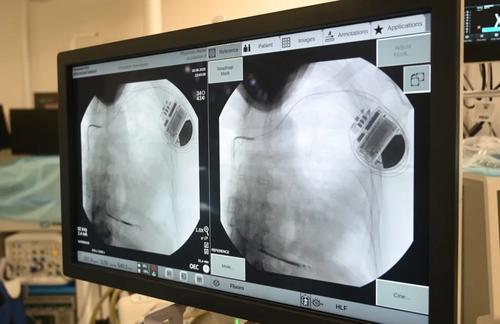

Подкожный кардиовертер-дефибриллятор устанавливается под широчайшую мышцу спины в подмышечной области, а электрод проводится подкожно на переднюю грудную стенку и устанавливается в проекции сердца. Прибор контролирует активность сердца и, когда оно останавливается, начинает биться неправильно, слишком медленно или слишком быстро, благодаря специальным алгоритмам аппарат посылает электрические импульсы, позволяющие восстановить нормальный сердечный ритм.

Впервые подкожную систему кардиовертера-дефибриллятора установили пациенту медики больницы им. В.В. Вересаева год назад. Сегодня такие вмешательства проводят в операционных ГКБ им. С.С. Юдина, ГКБ им. В.В. Вересаева и ГКБ им. И.В. Давыдовского.